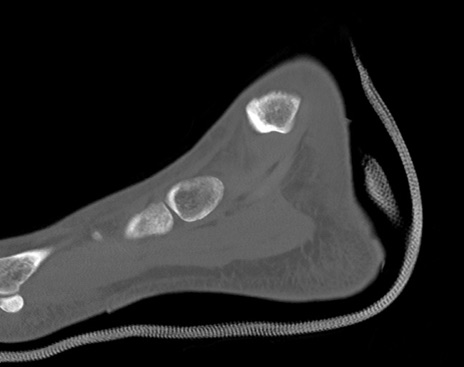

症例37 左足関節CT(矢状断像)

横断像